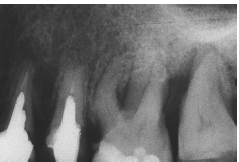

Al momento del examen, 10 (90.9%) EC estaban en función en 10 pacientes. Un molar 26, restaurado con EC, se perdió por enfermedad periodontal después de 12 años y 9 meses en función. Ninguna restauración se desprendió, no hubo recidiva de caries y al examen radiográfico no se observaron lesiones patológicas en los 10 DPET en función (Figs. 1a,1d; 2c; 3c,3d; 4c).

Situación inicial en #26. La raíz distovestibular debe ser amputada.

Preparación dentaria para EC en #26